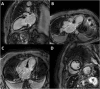

"Cases of SCMR" is a case series on the SCMR website (https://www.scmr.org) for the purpose of education. The cases reflect the clinical presentation, and the use of cardiovascular magnetic resonance (CMR) in the diagnosis and management of cardiovascular disease. The 2022 digital collection of cases are presented in this manuscript.

Keywords: Arrhythmogenic cardiomyopathy; COVID-19; Cardio-oncology; Congenital Heart disease; Coronary artery aneurysm; Hydatid disease; Hypertrophic cardiomyopathy; Metastatic disease; Myocardial. infarction; Myocarditis; Takotsubo; Vaccine associated myocarditis; Viability.